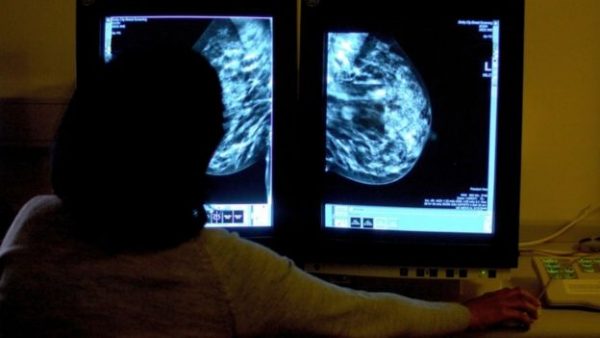

_95560286_038589788الحكمة – متابعة: خلصت دراسة حديثة إلى أن نسبة احتمال وفاة المصابات بسرطان الثدي اللاتي ينمن تسع ساعات على الأقل يوميا متأثرات بمرضهن أعلى من المريضات اللاتي ينمن ثمان ساعات.

ووفقا للدراسة، يزيد احتمال وفاة النساء اللاتي ينمن تسع ساعات على الأقل نتيجة لإصابتهن بورم في الثدي بنسبة 46 في المئة مقارنة بالنساء اللاتي ينمن ساعات أقل.

وبعد 30 عاما من المتابعة البحثية، خلصت الدراسة أيضا إلى أن النساء اللائي ينمن مددا أطول يزيد احتمال وفاتهن بأمراض أخرى بنسبة 34 بالمئة.

وقالت كلوديا ترودل-فيتزجيرالد كبيرة الباحثات في الدراسة، التي أجرتها كلية تي إتش تشان للصحة العامة في جامعة هارفارد في بوسطن إن “مدة النوم، والتغير في مدته بعد تشخيص الإصابة بالمرض وقبلها بالإضافة إلى الصعوبة في النوم أو صعوبة الاستمرار فيه، كلها عوامل تؤثر في احتمال وفاة المصابات بسرطان الثدي”.

وأوضحت ترودل-فيتزجيرالد أن “الدراسة كشفت أن الصلة بين مدة النوم والوفاة لا تقتصر فقط على النساء المصابات بسرطان الثدي بل هناك علاقة محتملة بينها وبين الوفيات بأنواع أخرى من السرطان. ولكن الأمر يتطلب المزيد من الأبحاث”.

ودرس الباحثون بيانات النوم الخاصة بـ 3682 امرأة سواء قبل أو بعد تشخيص إصابتهن بسرطان الثدي والصعوبات في النوم التي واجهتن بعد الإصابة.

وشملت الدراسة نساء كان معدل أعمارهن عند تشخيص الحالة نحو 65 عاما وكن مصابات بالمرحلة الأولى أو الثانية من سرطان الثدي، أي أن المرض لم ينتشر إلى أعضاء أخرى ولم يصل إلى الغدد الليمفاوية.

وبقى ما لا يقل عن نصف عدد النساء اللائي شملتهن الدراسة على قيد الحياة بعد 11 عاما من تشخيص إصابتهن بسرطان الثدي.